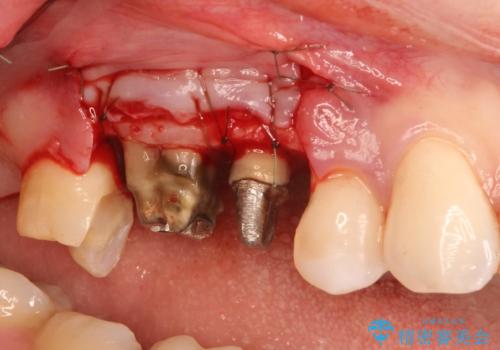

お引越しにより、上の前歯のインプラントおよび奥歯のセラミックの治療の続きを当院にて希望され、来院した患者様です。

一口にインプラントと言っても、メーカーや規格が様々あるため引継ぎは簡単ではないのですが、埋入されたインプラントのデータを治療された医院よりお持ちいただければ引き継ぐことが可能になります。

当院では、単純に埋入したインプラントを歯ぐきから出して上部構造を作るだけではなく、その後のインプラントの寿命のために、歯周病管理を必ず行います。この患者様も、お掃除などの基本的な歯周病治療だけでなく、歯周外科治療を行うことになりました。

歯根分割術は河野理事長が行っています。